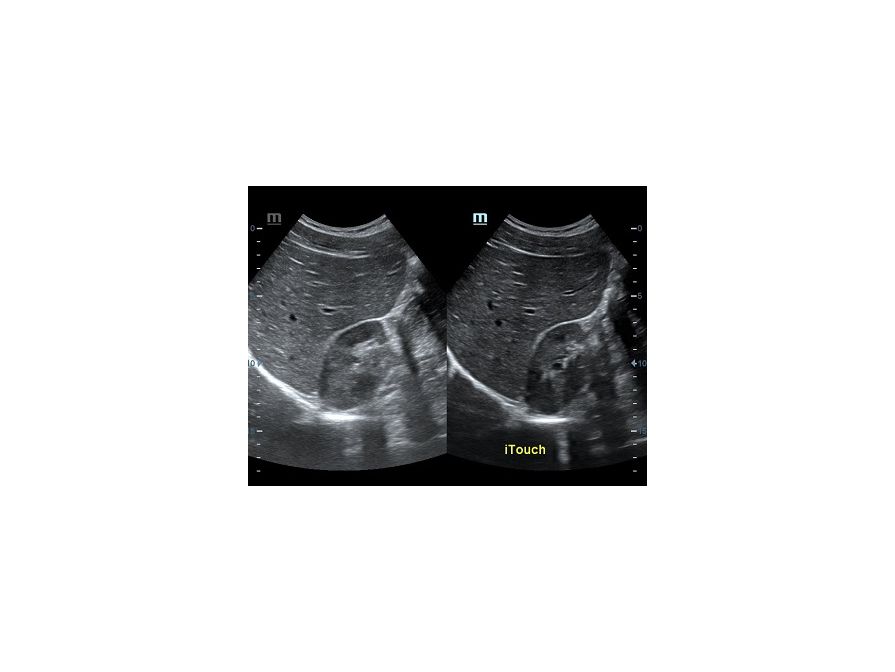

Ультразвуковая волна распространяется от пьезокристалла в направлении плоскости сканирования. Если волна отражается от поверхности исследуемой структуры под прямым углом и возвращается к пьезокристаллу напрямую, на сонограмме появляется четкая дифференцировка структуры и подчеркнутые контуры. Прямое отражение - самый важный критерий техники сканирования для измерения точных размеров органа. В случае отражения волны не под прямым углом эхогенность структуры меняется, дифференцировка на слои падает, контуры становятся нечеткими. Таким образом косой срез дает огромную погрешность измерения и затрудняет описание эхоструктуры объекта.

Как достичь прямого отражения Достаточно расположить объект на экране горизонтально, с помощью наклона датчика, чтобы волна отражалась от поверхности под прямым углом. При любом типе исследования любого органа или системы прямое отражение – залог достоверных результатов.